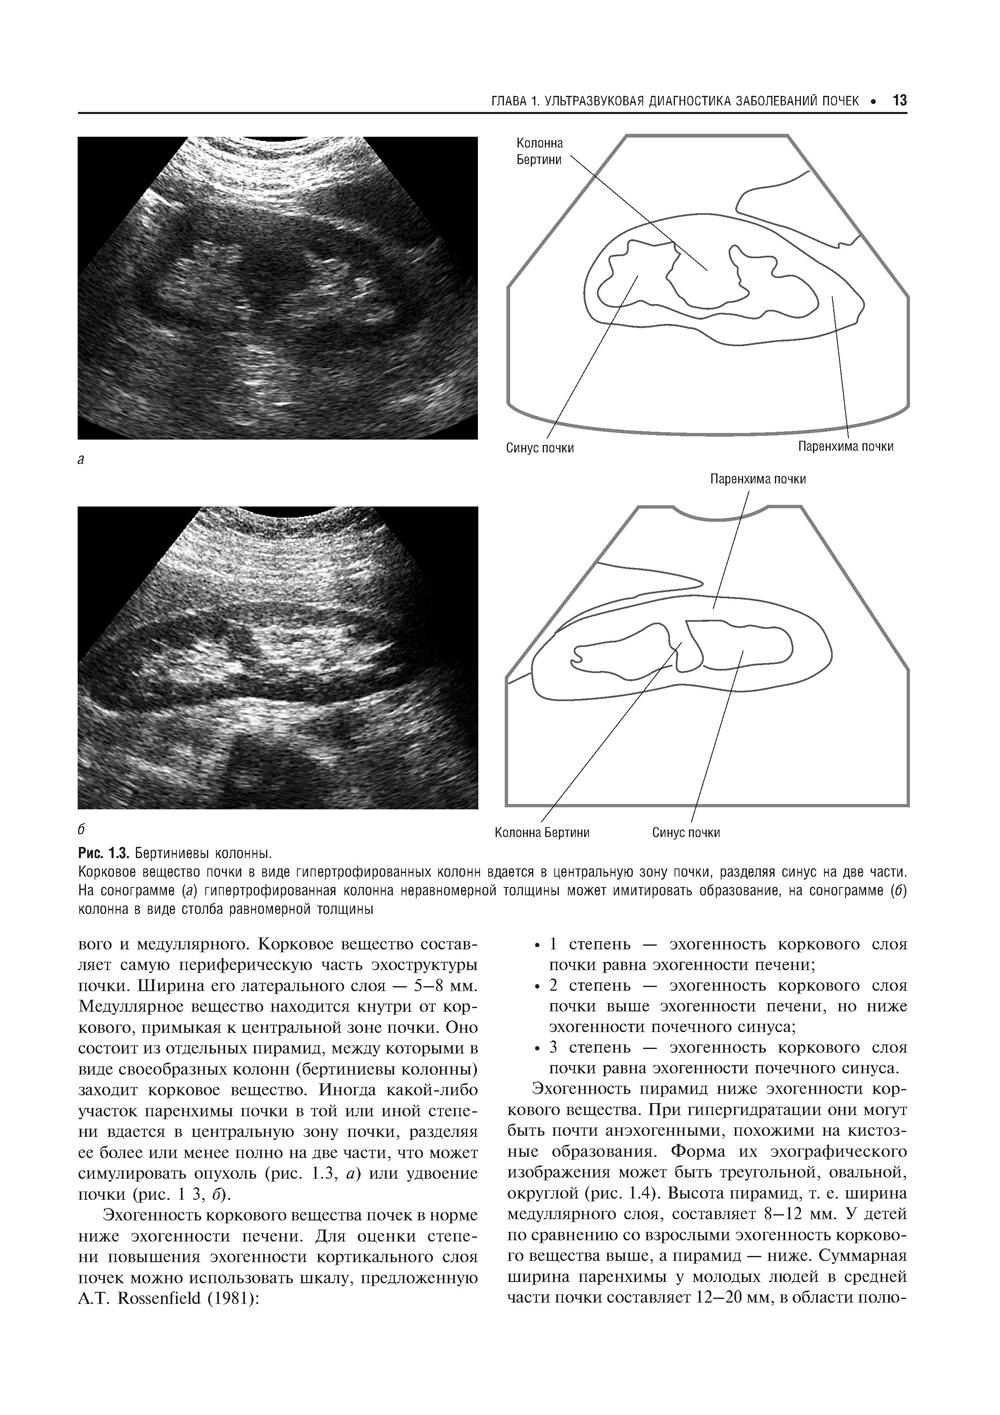

Второй том руководства рассказывает о применении различных методик ультразвукового исследования в диагностике заболеваний почек, мочеточников, мочевого пузыря и мочеиспускательного канала, мужских половых органов и надпочечников. Описывается нормальная ультразвуковая анатомия соответствующих органов, клиника и УЗ-семиотика наиболее часто встречающихся заболеваний и патологий. Отдельная глава посвящена неотложной УЗ-диагностике при острых заболеваниях и повреждениях мочевых органов. Издание адресовано слушателям, обучающимся в системе послевузовского профессионального дополнительного образования, а также специалистам по лучевой диагностике, врачам, работающим в кабинетах и отделениях ультразвуковой диагностики.